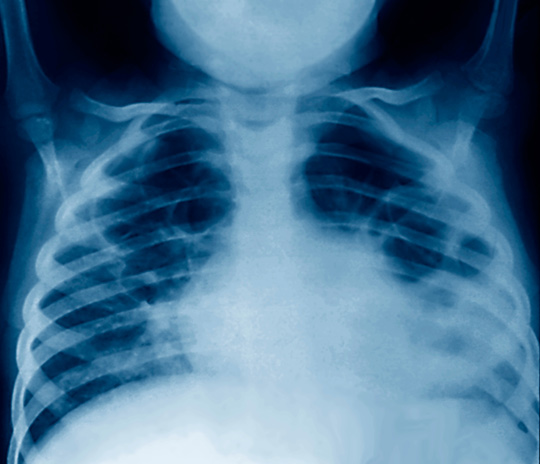

Diagnosen pneumoni ble stilt hos barn med hoste eller pustevansker og aldersspesifikk takypné eller hvis det ble observert respiratoriske inndragninger i brystkassen. Vaksinasjonsdekningen blant deltakerne var høy for vaksiner gitt de første tre levemånedene, men sank til 75 % for den tredje dosen av en 13-valent pneumokokkvaksine som gis ved ni måneders alder.

Det ble registrert totalt 141 tilfeller av lungebetennelse i første leveår, hos 109 av studiedeltakerne. Av disse var litt under en firedel kategorisert som alvorlige tilfeller. Ut fra dette ble insidensen av lungebetennelse hos barn under ett år beregnet til 0,27 episoder per personår (95 % KI 0,23 – 0,32). To barn døde som følge av lungebetennelse.